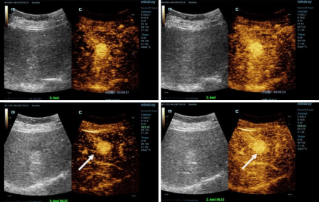

![more-precise-diagnoses-with-hifr-ceus.thumb.319.319 Genauere Diagnosen mit HiFR-CEUS]() Genauere Diagnosen mit HiFR-CEUSKontrastmittelverst?rkter Ultraschall (CEUS oder KM-Sonografie) ist ein au?erordentlich dynamisches Feld, auf dem in den letzten Jahren weitere technologische Innovationen zur Verbesserung der Bildqualit?t erreicht werden konnten. Eine dieser Innovationen ist der kontrastmittelverst?rkte Ultraschall mit hoher Bildrate (HiFR-CEUS), der im Vergleich zu herk?mmlichem Ultraschall bis zu zehnmal so viele Bilder liefert ŌĆō in derselben Zeit.Ultraschall | Allgemeine Bildgebung 2022-12-16

Genauere Diagnosen mit HiFR-CEUSKontrastmittelverst?rkter Ultraschall (CEUS oder KM-Sonografie) ist ein au?erordentlich dynamisches Feld, auf dem in den letzten Jahren weitere technologische Innovationen zur Verbesserung der Bildqualit?t erreicht werden konnten. Eine dieser Innovationen ist der kontrastmittelverst?rkte Ultraschall mit hoher Bildrate (HiFR-CEUS), der im Vergleich zu herk?mmlichem Ultraschall bis zu zehnmal so viele Bilder liefert ŌĆō in derselben Zeit.Ultraschall | Allgemeine Bildgebung 2022-12-16 -